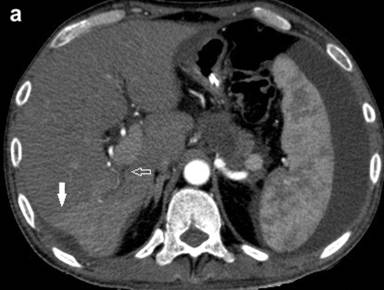

Pancreatitis-associated THAD may arise because of inflammation induced increase in arterial inflow (polymorphous type) [27] or thrombosis in portal, splenic or superior mesenteric veins (sectorial or diffuse type). A sectorial type occurs in the setting of thrombosis of portal vein and typically has a wedge shaped or at least one straight border [23, 27]. When the thrombus is present in the main PV trunk, collaterals in the peri-hilar region maintain perfusion of the central portion. The periphery however, continues to receive undiluted contrast carried by hepatic artery branches with consequent high attenuation of the periphery. Such a pattern is called central-peripheral subtype of diffuse THAD (Figure 4) [27].

|

Figure 4 a. CECT arterial phase demonstrated a sectorial type of transient hepatic attenuation difference with a straight border (solid arrow). Also noted are thrombosis in a tributary of portal vein (arrow) with fluid collection in the body of pancreas. b. CECT venous phase shows near complete resolution of transient hepatic attenuation difference with thrombosis in a tributary of portal vein (arrow). |